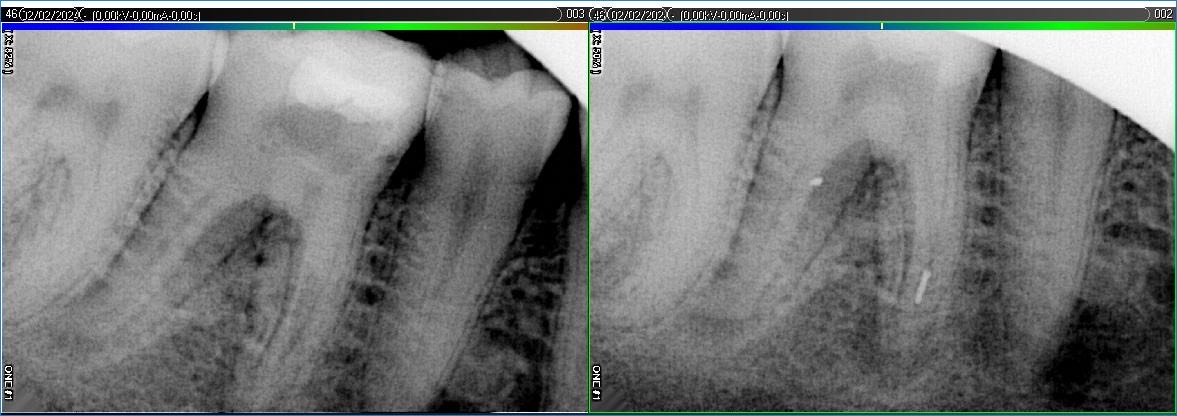

Вилучення інструменту з каналів зуба